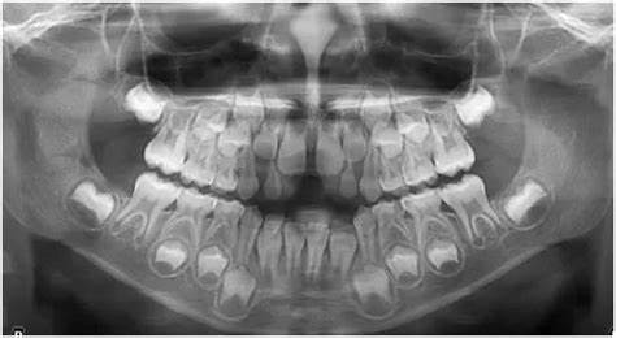

恒牙迟萌原因多种多样:

恒牙胚坏死、缺失或者错位。

多生牙、牙瘤或囊肿的阻碍。

怀疑是恒牙迟萌,该怎么办?